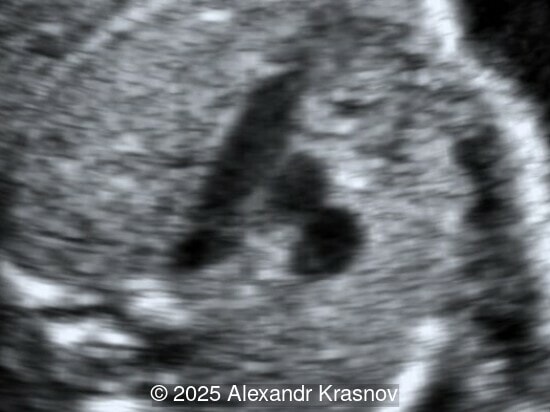

Our ultrasound showed biometry data corresponding to 21 weeks of gestation. During echocardiography, an abnormal drainage of the pulmonary veins was detected in which the pulmonary veins drain into a venous collector linked to the superior vena cava. The four-chamber view and the three-vessel view were altered and raised suspicion of a pathology. The grayscale and color Doppler images of the four-chamber view indicate a smooth posterior wall of the left atrium, increased distance between the left atrium and the descending aorta and the absence of pulmonary veins entering the left atrium (Image 1, 2; Video 1, 2). In the three-vessel view, the diameter of the superior vena cava appears larger than that of the aorta (Image 3, Video 3). In the images of the venae cava, a significant difference is seen between the diameters of the inferior and superior vena cava with significant enlargement of the superior vena cava (Image 4, Video 4). Additionally, there is a pulmonary venous confluent chamber (“twig sign”) behind the left atrium (Image and Video 5). A vertical ascending vein connects the confluent chamber with the superior vena cava where it drains blood from the pulmonary veins (Images 6, 7; Video 6).

Direct markers are based on anatomical features in TAPVR, and their presence usually confirms the diagnosis. Some appear in all types of TAPVR, and others are specific to particular types. A lack of connection between the pulmonary veins and the left atrium or the presence of a confluent chamber can be found in all types of TAPVR. Whereas the presence of an ascending or descending vertical vein is found in supracardiac or infracardiac types. Normal entry of a left and right pulmonary vein at the posterior wall of the left atrium (horn‑like insertion) is absent, which leads to a completely smooth posterior wall in the four-chamber view [6,7]. The “twig sign” represents the entry of the pulmonary veins into a confluent chamber behind the left atrium [7], and is visible in the four‑chamber view except in the cardiac type. In the cardiac type, the confluent vein is located more inferiorly, below the plane of the four‑chamber view and does not form a twig sign, making it more difficult to detect [5]. In supracardiac TAPVR, an ascending vertical vein can be observed in the 3-vessel tracheal view as an additional vessel, usually located at the left of the main pulmonary artery. In infracardiac TAPVR, the descending vertical vein can be seen as an additional vein in the axial abdominal plane [8].

In many cases, direct signs are not visualized, thus identification of indirect signs allow us to suspect this pathology, not diagnose it. They are based on morphological findings such as increased post‑left atrium space, or on hemodynamic changes such as ventricular disproportion, dilated superior vena cava or coronary sinus, and abnormal Doppler waveforms. The presence of a pulmonary venous confluence leads to an increased distance between the left atrium (LA) and the descending aorta (DAo) [9]. While visualization of the confluent chamber may be difficult, objectively measuring the increase in the space behind the left atrium in an axial section may be easier to verify. Various indices have been proposed for this purpose, the most widely used being the “post‑LA space index” described by Kawazu et al [10]. It is calculated as the ratio of the LA‑DAo distance to the diameter of the DAo, proposing a value ≥1.27 as a potential marker of TAPVR. In clinical practice, a cut-off of 1.0 may be more useful to increase detection rates, although this would be at the expense of more false positives. An alternative marker with a similar diagnostic performance and independent of the gestational age is the “left atrial posterior space to diagonal ratio,” which is calculated by dividing the LA‑DAo distance by the left atrial diameter, with an optimal cut-off ≥0.35 [11]. Asymmetric ventricular chamber dimensions with right heart dominance result from extra‑abnormal flow from the pulmonary veins to the right heart, providing a diagnostic clue for TAPVR [9], but this finding is late and not very specific. In supracardiac TAPVR, anomalous pulmonary venous drainage increases blood flow to the collector, which travels to the right atrium through the dilated innominate vein and superior vena cava, visible in the three-vessel trachea and bicaval views [7,12]. In the subcostal view of pediatric echocardiography, the cardiac type is characterized by the “whale’s tail sign,” where left and right pulmonary veins drain into the dilated coronary sinus. Although it is a technically difficult plane to obtain in fetal echocardiography, it has been described by Karmegaraj in a 25-week-old fetus [13]. Spectral Doppler waveforms are typically normal or biphasic in cardiac type, whereas in supracardiac and infracardiac types, the waveforms can be biphasic, monophasic, or continuous [6,7]. Color and spectral Doppler assessment allows the identification of the fetuses with pulmonary venous pathway obstruction and, therefore, at risk for acute postnatal deterioration with severe respiratory distress and cyanosis [14].